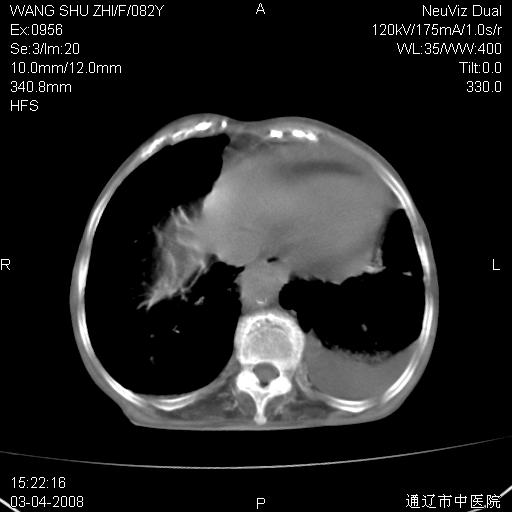

该患者为女性,82岁,既往肺心病、心衰病史。上纵隔影增宽,是否为畸形扩张的血管呢?因该患者年龄太大,又有较严重心脏病,故不适宜做增强检查。

中纵隔肿块最多见是淋巴瘤,而且以hd为多见,呈侵袭性生长,纵隔脂肪间隙消失,再加上心包和双侧胸腔积液,考虑为淋巴瘤(hd)应该说比较准确的。至于说是畸形的血管可能性小,因为畸形血管周围脂肪间隙应该存在。

纵隔淋巴结转移或淋巴瘤;双侧胸腔积液,心包积液。肺窗呢?

病史太简单,年龄太大,首先考虑转移!左侧腋窝亦见肿大淋巴结。

左侧腋窝及纵隔内见多个肿大淋巴结影,左侧少量胸腔积液,心包积液,支持淋巴瘤可能性大,不除外淋巴结转移。